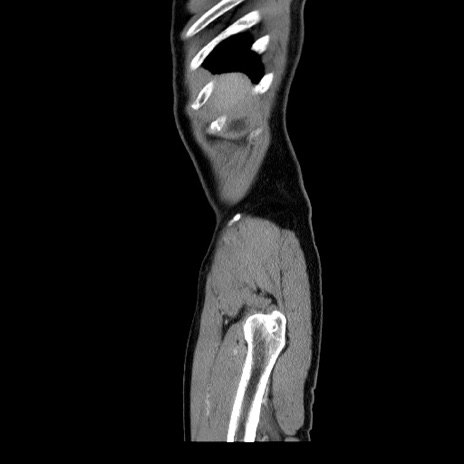

症例34(矢状断像)

【症例】60歳代 男性

【主訴】右鼠径部膨隆

【現病歴】1年程前より右鼠径部膨隆あり。自己にて還納可能だったため放置していた。3時間前より右鼠径部の脱出を認め、還納困難となり受診。

【既往歴】高血圧

【身体所見】右鼠径部に小児頭大の膨隆あり。弾性硬であり、用手還納は困難。左鼠径部にも膨隆を認める。脱出はなし。

【データ】WBC 15500、CRP 測定なし